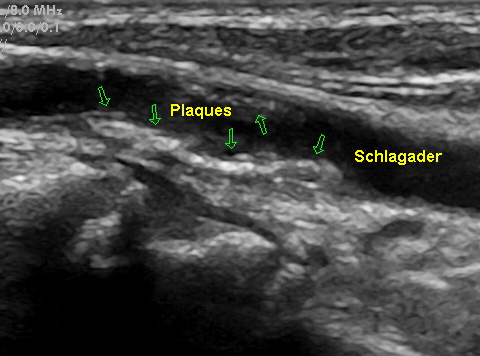

Auf den Bildern sehen Sie einerseits eine glatte Halsschlagader, die Sie schon als solche

erkennen können, weiter eine Halsschlagader mit beginnender Ablagerung (Plaques) und

eine Halsschlagader mit deutlichen Plaquebildungen bis insgesamt zu einer mindestens

70 %igen Verengung. Das erkennt man an dem schwarzen noch offenen Lumen.